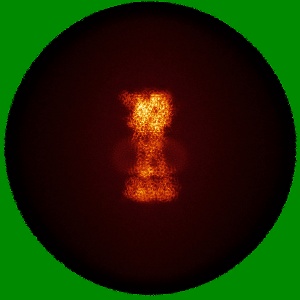

Cryo-EM structure of the human P2X7 receptor in the UB-MBX-46-bound inhibited state

Single-particle2.53 Å

Fitted models: 9e3p